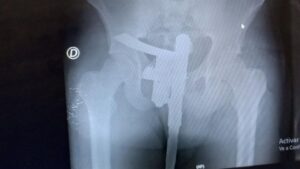

Un insólito hecho ocurrió en la mañana del domingo en el hospital José María Cullen de la ciudad de Santa Fe. Un enfermero que estaba de turno en el área de radiografías se sorprendió al descubrir en una placa que uno de los pacientes tenía un arma escondida entre sus ropas.

Se trataba de un joven de 25 años que había llegado al centro de salud producto de un accidente. Si bien no presentaba heridas de gravedad decidieron hacerle una placa para descartar lesiones internas.